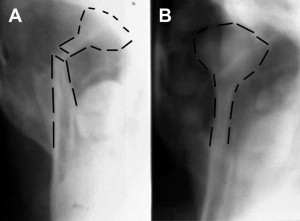

It does not matter to me whether the unilateral condylar fracture is intracapsular, condylar neck, or subcondylar. Nor does the degree of displacement matter to me. (It does not matter to me if there is a condyle. Unilateral condylectomy patients can readily be treated nonsurgically with excellent outcomes.) They can all be managed effectively if the criteria listed earlier are met. However, one must understand completely that, when one chooses closed treatment, especially those with large displacements, the neoarticulation does not translate as much as the nonfractured side. The consequence of this situation in the skeletally mature patient is that they often deviate toward the side of fracture when the mouth is opened (see Fig. 1 A in the techniques section) and they have limited lateral excursion away from the side of fracture ( Fig. 1 ). When they protrude their mandible, they also deviate toward the side of fracture. This deviation is not a failure of treatment; it is a consequence of the alteration in biomechanics secondary to the displaced condyle and the altered lateral pterygoid function. It is of no clinical consequence to the patient. That is not to say that patients treated open for unilateral condylar fractures do not do well. They usually do well, assuming that no injuries occur from the surgery to reduce and stabilize the condyle. However, one has to consider the risk/benefit ratio when deciding on treatment. If one can obtain a good occlusion, good facial symmetry, and pain-free function by treating someone closed, why should they risk the potential intraoperative and postoperative complications that are associated with open treatment?